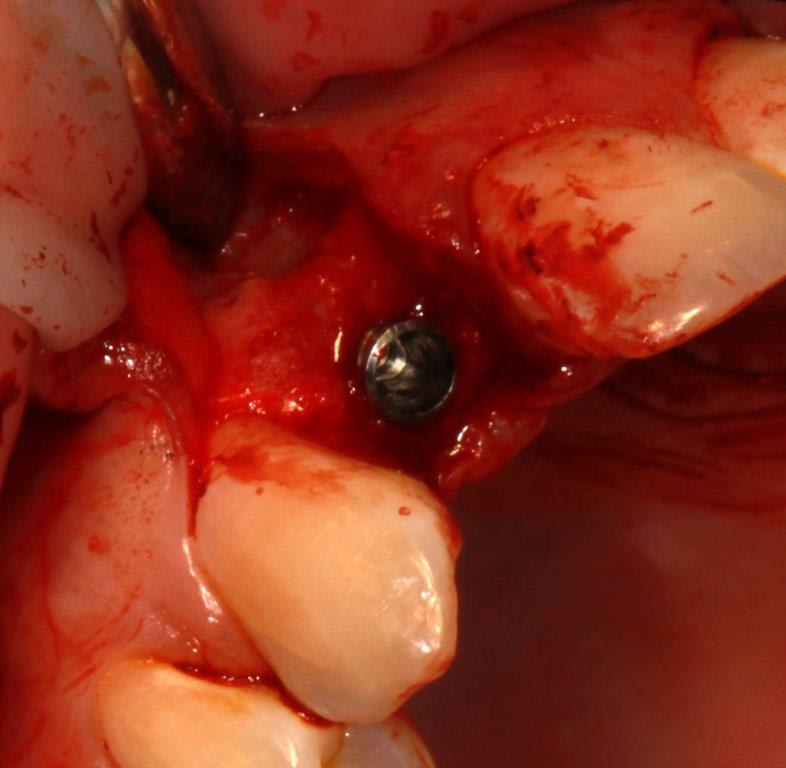

pour ceux que ça intéressent, une petite utilisation d'expansion de la paroi palatine, sur une avulsion d’incisive(racine fendue). toutes mes excuses pour la mauvaise qualité des photos.

Et à ton avis pourquoi ton incisive s'est fendue ? Y a qu'à regarder ta photo ...

Et donc tu mets un Implant dans ce contexte là .... faudra pas se demander pourquoi il y aura des complications prothétiques de type fracture de vis